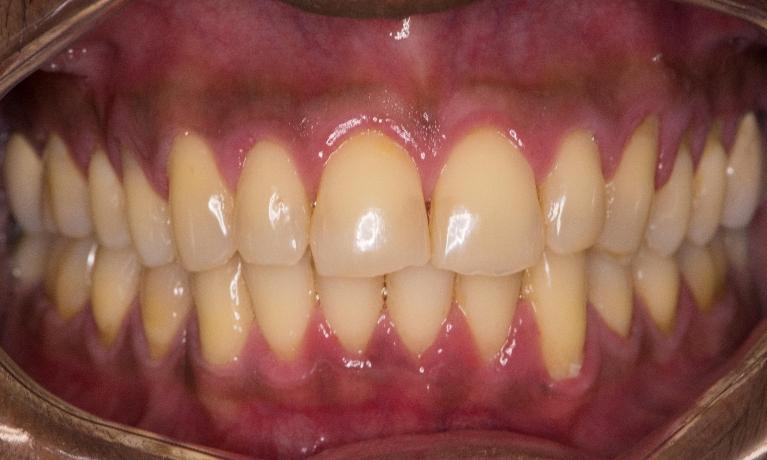

Laser gingivectomy(gum lift) to fix gummy smile and zoom whitening to lighten teeth color